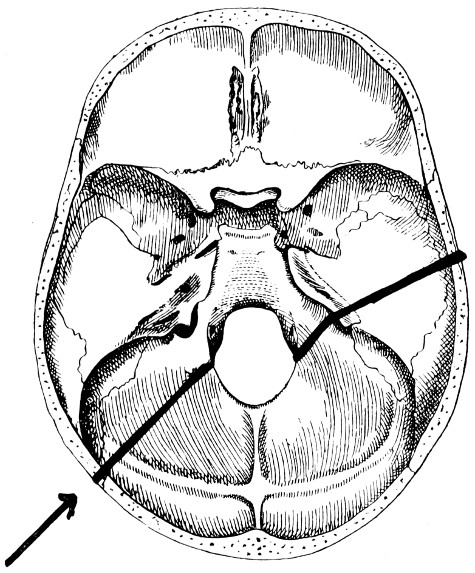

31. To illustrate the relation of basic fractures to cranial nerves 81

32-37. The lines pursued by basic fractures 83-8

38 A and B. To illustrate the probable source of profuse hæmorrhage from the ear 97